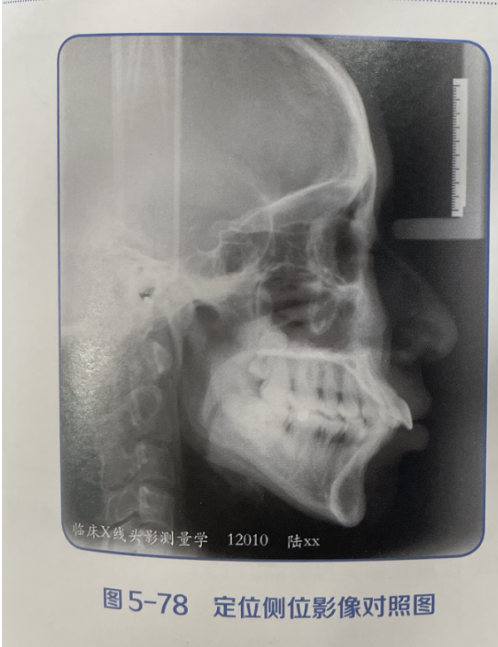

演示图片3

精确识别头颅侧位片中17个关键解剖标志点